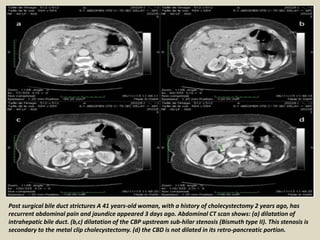

Post surgical bile duct strictures A 41 years-old woman, with a history of cholecystectomy 2 years ago, has

recurrent abdominal pain and jaundice appeared 3 days ago. Abdominal CT scan shows: (a) dilatation of

intrahepatic bile duct. (b,c) dilatation of the CBP upstream sub-hilar stenosis (Bismuth type II). This stenosis is

secondary to the metal clip cholecystectomy. (d) the CBD is not dilated in its retro-pancreatic portion.

Post surgical bileduct strictures A 41 years-old woman, with a history of cholecystectomy 2 years ago, has recurrent abdominal pain and jaundice appeared 3 days ago. Abdominal CT scan shows: (a) dilatation of intrahepatic bile duct. (b,c) dilatation of the CBP upstream sub-hilar stenosis (Bismuth type II). This stenosis is secondary to the metal clip cholecystectomy. (d) the CBD is not dilated in its retro-pancreatic portion.